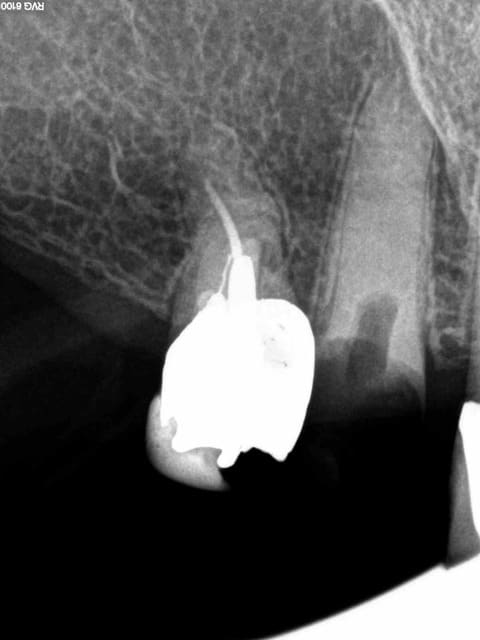

Arrivé un moment ou tu te dis que tu vas l'extraire, mais tu ne le fais pas parceque ca fait 3/4 d'heures que tu cherches ce putain de canal. Et enfin la lumière fut ( c'est le cas de le dire). -)))))

1 nfmvd7 - Eugenol

2 dvdqtt - Eugenol

3 f3ohf3 - Eugenol

4 zmohou - Eugenol

5 j0htr8 - Eugenol

6 e86kdq - Eugenol

7 fbttie - Eugenol